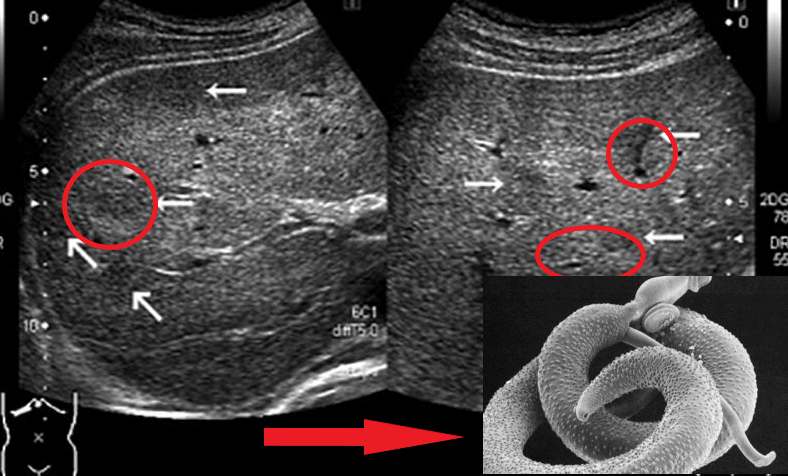

"Căile" paraziților în lumenul intestinal

Reprezentanții helminților care afectează organele vitale sunt Taenia solium, Echinococcus (Echinococcus granulosus), Trichinella (Trichinella spiralis). Echinococul este o etapă larvară a unui helmint din genul Echinococcus. Și acestea nu sunt tot felul de paraziți care pot ucide o persoană.